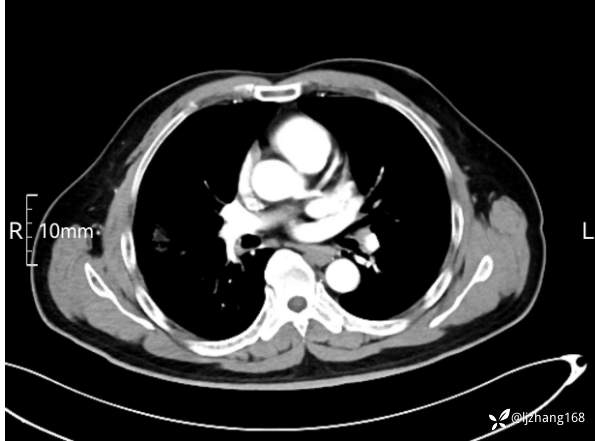

中年男患,右肺团片影,炎症0R肿瘤?

辅助检查:糖化血红蛋白12.3%。肺炎支原体IgG、IgM、呼吸道合胞病毒均未见明显异常。胸部CT:右肺上叶阻塞性肺炎。